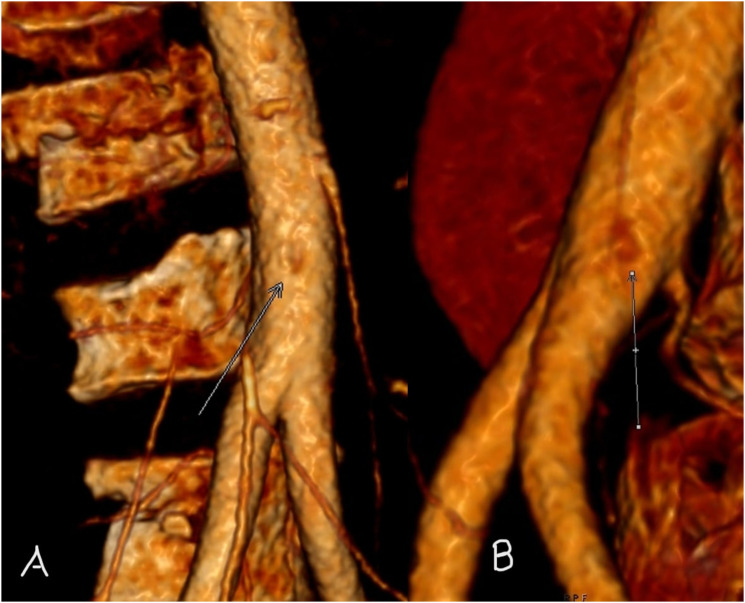

背景:随着越来越多地使用成像技术诊断人体病理,越来越多新的主动脉异常被发现。主动脉内索就是这样一种异常,需要与夹层的内膜瓣区分开来,以避免大手术或长期监护。本研究的目的是利用容积渲染重新格式化技术,提出主动脉内索在成像上的独特特征,并确定已发表文献中的类似发现,从而确定 "小酒窝 "征的作用:方法:回顾本院的成像(2 例)和已发表的文献(6 例),以确定主动脉容积渲染成像中是否存在诊断征象:结果:"酒窝征 "是主动脉内索特有的征象,在之前发表的 6 篇文献中,有 4 篇的图像中出现了这一征象。有两篇文章没有使用容积渲染。包括我们的病例在内,8 个病例中有 6 个出现了 "酒窝征"。出现 "酒窝 "征的原因是脐带拴系在主动脉壁上,导致主动脉壁向内脐化发展:结论:"酒窝 "征在容积和/或电影渲染中很容易观察到,是诊断主动脉内脐带的有用征象,有助于将其与内膜瓣区分开来。

BackgroundWith increasing use of imaging to diagnose human pathology, newer aortic anomalies are being identified. An intra-aortic cord is one such abnormality, which requires differentiating from an intimal flap of dissection, to avoid major surgery or prolonged surveillance. The aim of this study was to bring forth a unique feature of the intra-aortic cord on imaging, using volume rendering reformatting and identify similar findings in published literature and hence establish the role of the 'Dimple' sign.MethodsReview of both our institutional imaging (2 cases) as well as the published literature (6 cases), to identify presence of a diagnostic sign that is seen on volume rendered imaging of aorta.ResultsThe 'Dimple sign' is unique to the intra-aortic cord and is noted on the images of 4 out of 6 prior publications. Two publications did not use volume rendering. Including our cases, the Dimple' sign is seen in 6 out of 8 cases. The Dimple sign arises due to tethering of the cord to the aortic wall leading to umbilication of the aortic wall inwards.ConclusionsThe Dimple sign can be very easily noted on volume and/or cinematic rendering and is a useful sign to diagnose an intra-aortic cord and help differentiate it from an intimal flap.